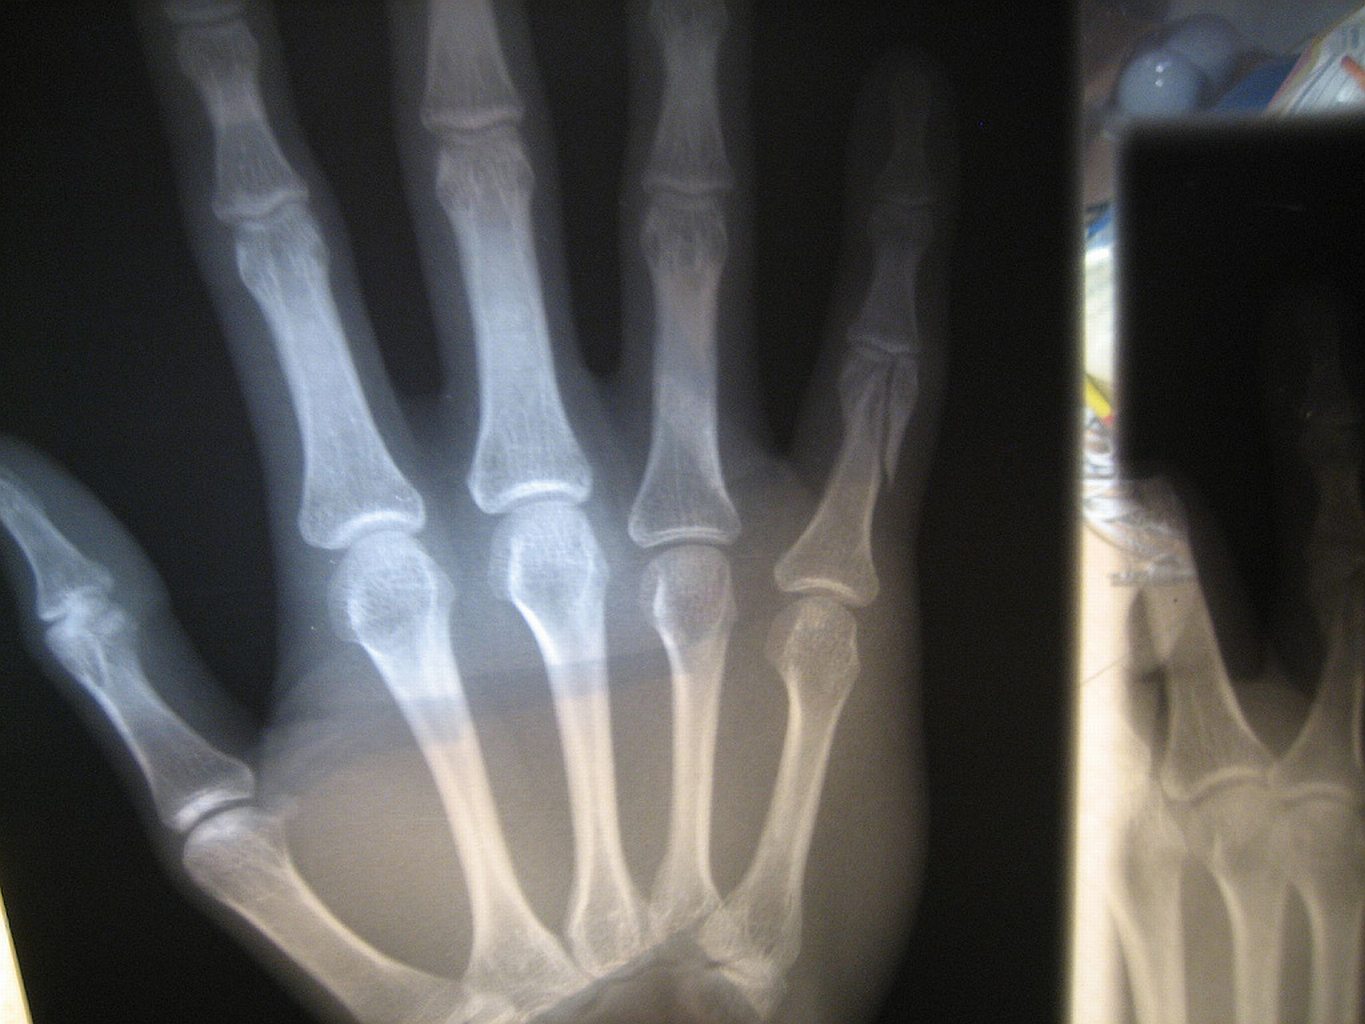

Zagrożenie wynikające z wykonania jednego zdjęcia jest niewielkie, ale z każdą kolejną dawką promieniowania ryzyko dla zdrowia rośnie. Zagrożenie wynikające z wykonania jednego zdjęcia jest niewielkie, ale z każdą kolejną dawką promieniowania ryzyko dla zdrowia rośnie. keone / Flickr CC by SA

Kilkanaście procent skierowań na badania z wykorzystaniem promieniowania rentgenowskiego jest wydawanych na wyrost.Alamy/BEW Kilkanaście procent skierowań na badania z wykorzystaniem promieniowania rentgenowskiego jest wydawanych na wyrost.